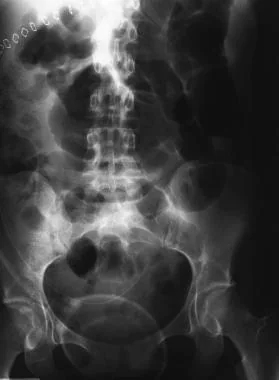

Ileus는 생리적인 neural signaling이나 neurohormonal networks가 제대로 기능하지 않을 때 발생할 수 있으며 그 원인은 다음과 같다:

증가된 sympathetic activity에 의한 억제성 neuroenteric signaling

bowel wall이나 그 주변 구조물의 inflammation

억제성 gastrointestinal peptide나 endogenous opioid의 paracrine, endocrine activity

진통 목적의 exogenous opioids 투여

수술 후 발생하는 ileus

복부 수술 후에 ileus가 흔하게 올 수 있다. 보통 small bowel motility는 수술 후 24시간 이내에 돌아오고, gastric motility는 24에서 48시간 이내에, colonic motility는 48에서 72시간 이내에 돌아온다고 알려져 있다.

만약 수술 후 bowel motility가 돌아오는 기간이 일반적인 예상 기간을 넘어가는 경우(개복 수술은 5일, 복강경 수술은 3일),

pathologic postoperative ileus를 의심해야 하며 그 원인을 찾아야 한다.